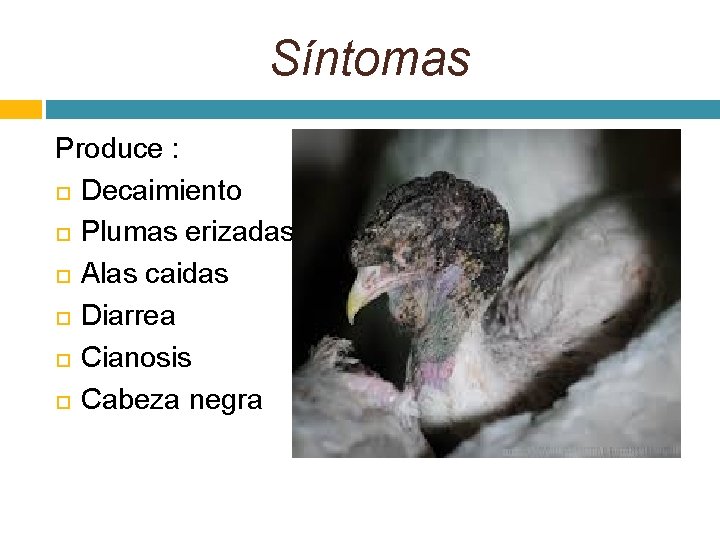

Síntomas Produce : Decaimiento Plumas erizadas Alas caidas Diarrea Cianosis Cabeza negra